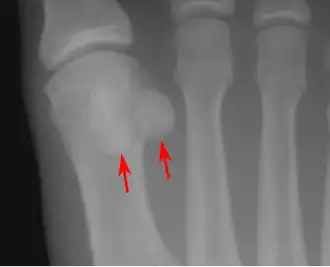

- In the foot—the first metatarsal bone usually has two sesamoid bones at its connection to the big toe (both within the tendon of flexor hallucis brevis).[10] One is found on the lateral side of the first metatarsal while the other is found on the medial side. In some people, only a single sesamoid is found on the first metatarsal bone.

- One or both of the sesamoid bones under the first metatarsophalangeal joint (of the great toe) can be multipartite – in two or three parts (mostly bipartite – in two parts).[12]

Lateral view.[11] -

Bipartite medial sesamoid bone under the first metatarsophalangeal joint of the great toe of the left foot of an adult woman.